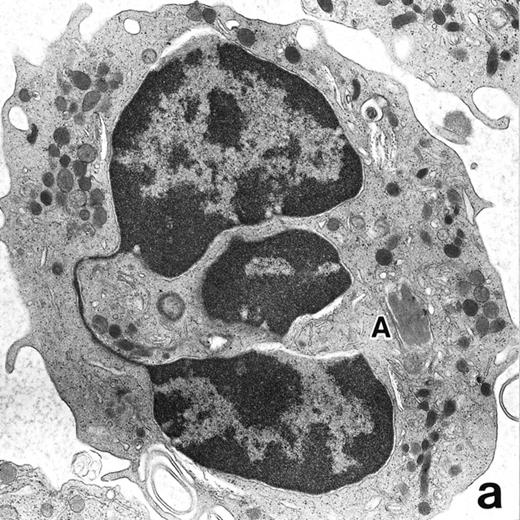

(a) A bone marrow leukemic cell in patient no. 1 at diagnosis containing abundant abnormally shaped primary granules, including Auer rods and Chediak-Higashi–type inclusions. Dilatation of rER is remarkable. (Original magnification × 10,800.) (b) Higher magnification of a cytoplasmic inclusion body of another cell in patient no. 1 that is membrane-bound and contains bundles of filamentous structures, similar to Auer rods. (Original magnification × 25,800.)

Electron microscopic observation.The leukemic cells of all three patients possessed abundant spherical (type I) primary granules containing electron-dense homogeneous material, with a peripheral halo in some granules and dilated rER (Fig 2a). Although type I primary granules predominated in all patients, small numbers of cytoplasmic granules containing crystalloid structures (type II primary granules) were also present in patient no. 1. Nuclear configurations were irregular, and the chromatin was only slightly condensed along the nuclear membrane. In addition to numerous Auer rods, the cells of patient no. 1 contained large cytoplasmic inclusion bodies also seen under the light microscope. These are the structures surrounded by a unit membrane and filled with parallel tubular material identical to that of Auer rods and belong to the psuedo–Chediak-Higashi (C-H) category of granules20,27 (Fig 2b). The cells of patient no. 3 contained smaller cytoplasmic granules than those of the other patients, and Auer rods were less frequently observed, a finding consistent with the M3 variant. Stellate rER complexes and fibrillar structures in the rER, both of which are thought to be structures specific to APL,28 were detected in this patient.